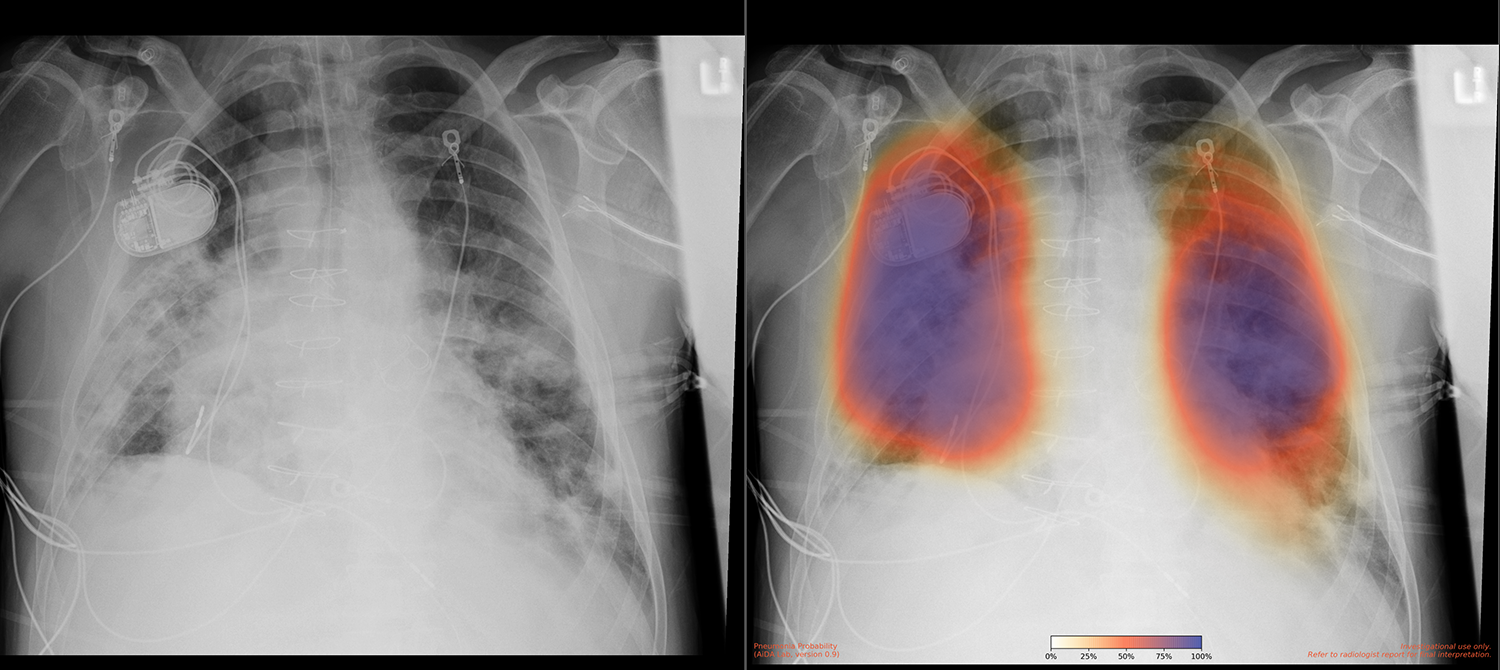

加州大學圣地亞哥分校健康中心是全球排名前15位的研究型大學之一。加州大學圣地亞哥分校醫(yī)學院每年進行數(shù)百項臨床試驗,加州大學圣地亞哥分校健康服務研究中心專門從事健康結果數(shù)據的收集和分析,以支持研究。2018年,由加州大學圣地亞哥分校醫(yī)學院放射學副教授Albert Hsiao博士領導的加州大學圣地亞哥分校健康中心一個團隊開發(fā)了一種使用機器學習在X射線圖像中檢測肺炎的方法。“我們創(chuàng)建了一個帶有顏色編碼的概率圖,表明肺炎的不確定性或確定性,”蕭醫(yī)生團隊的住院醫(yī)師Brian Hurt博士說。根據Hsiao博士的說法,“人們通常做的是創(chuàng)建一個模型,給出一個簡單的是或否輸出,表明它是否是肺炎。但我們認為,制作圖像對于突出異常位置非常重要。該團隊在2020年初發(fā)表了一篇關于這些結果的論文。

COVID-19 肺炎患者的胸部 X 線檢查、原始 X 線檢查(左)和肺炎 AI 結果(右)?;颊哂幸粋€起搏器裝置和一個擴大的心臟,這表明人工智能算法足夠強大,即使患者有潛在的健康問題也能工作。